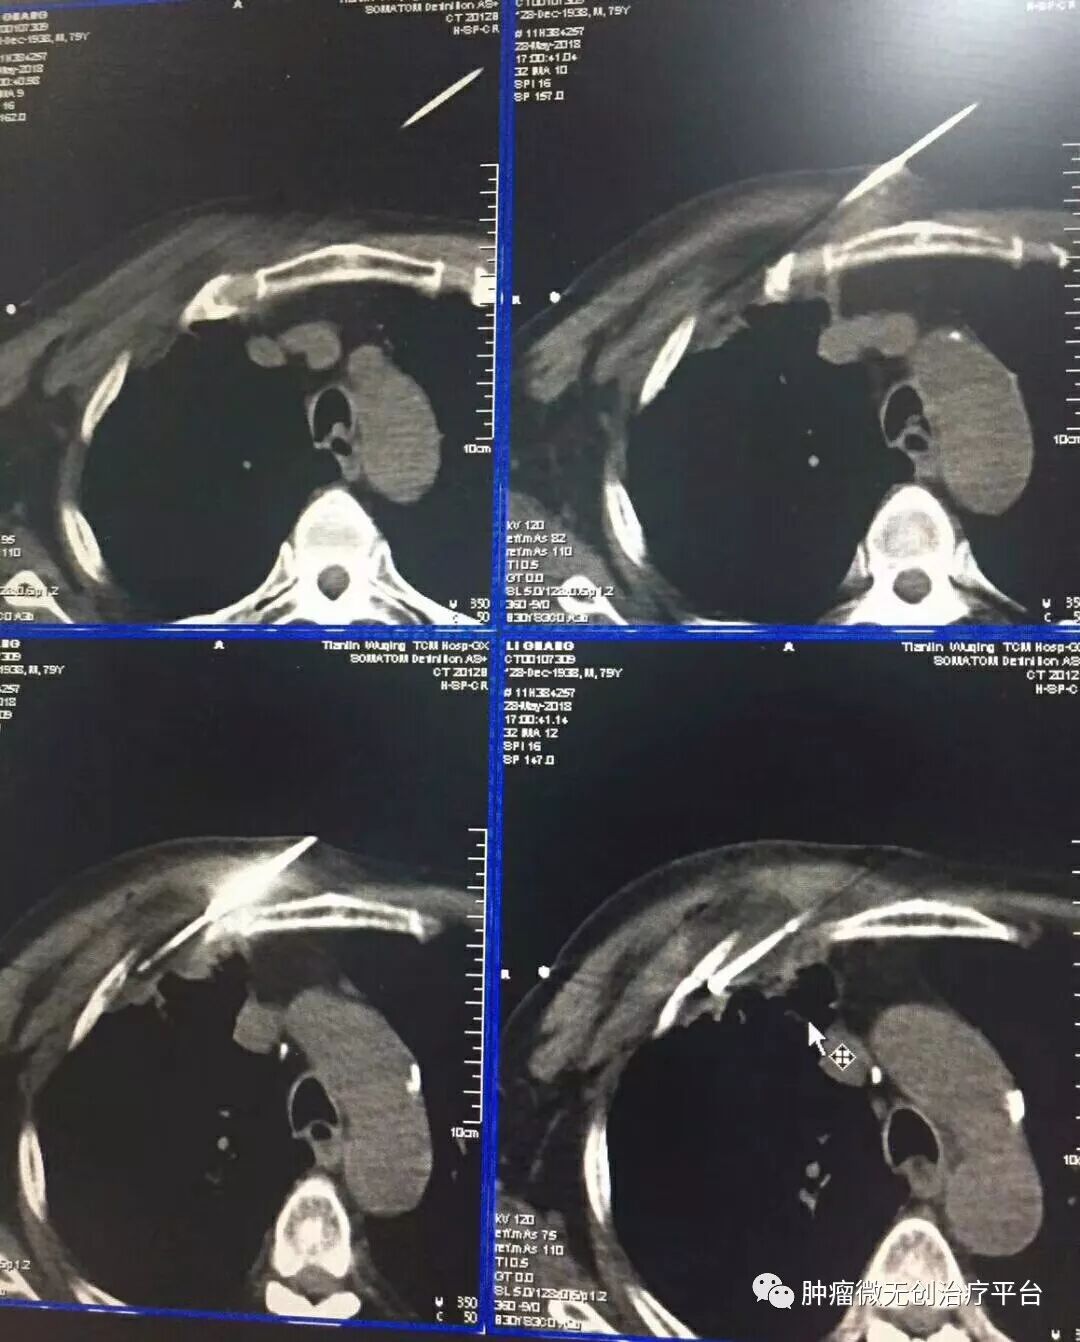

正文:5月28日,右肺腺癌侵犯胸壁患者,在天津市武清区中医医院胸外科进行氩氦刀冷冻消融治疗。

患者情况高龄(79岁)右肺腺癌侵犯胸壁患者肿瘤供血动脉栓塞➕氩氦刀冷冻消融术:图1-2术前PET-CT;图3术前CT;图4-5肿瘤供血动脉栓塞介入;图6-9氩氦刀冷冻消融治疗。